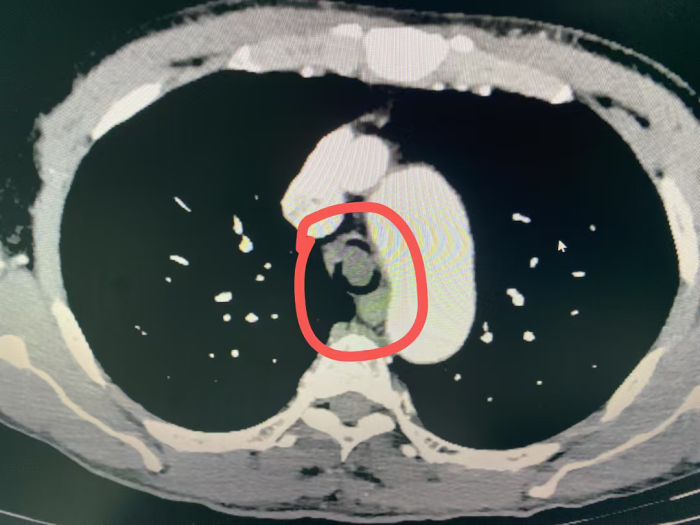

同样呼吸困难的情况也发生在54岁的黄先生身上,黄先生因食管癌晚期,在外院经多次放疗和化疗后疾病仍进展,春节期间突发明显呼吸困难至当地医院就诊,当地医院完善肺部CT后发现黄先生的食管肿瘤已严重压迫气管,气道呈现“一线天”改变,最狭窄处仅剩余5mm不到。

看着黄先生痛苦不已,家属心急如焚,打听到自治区南溪山医院院呼吸与危重症医学科二病区有神奇的呼吸介入手术可缓解呼吸困难,遂于春节期间紧急转至该病区。屈东明博士查看资料后迅速组织完善术前检查,呼吸介入团队联合麻醉科、内镜中心联合制定个性化方案。在全麻下行沙漏型硅酮支架植入术,术中发现患者情况更为严重,因肿瘤侵犯气管扭曲,鞘管无法通过最狭窄部位,同时支架推送器也无法通过鞘管。呼吸介入团队经过商量后迅速调整手术方案,终于成功植入气道支架,患者从“命悬一线”到自由呼吸!